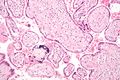

Micrograph of CMV placentitis.